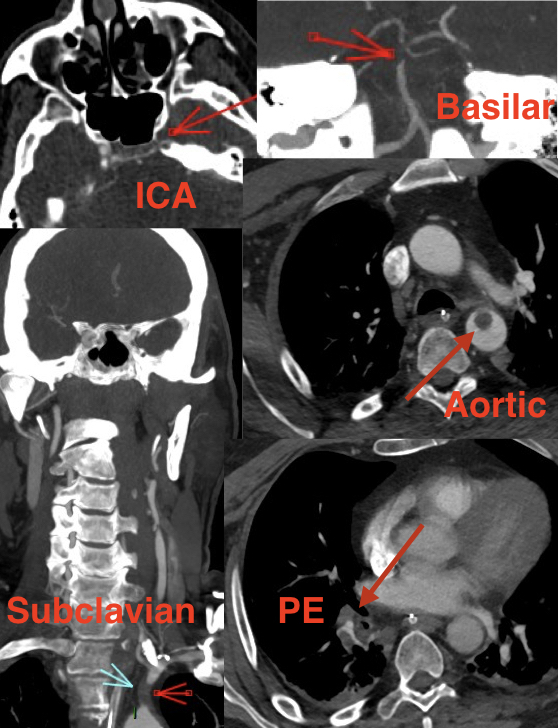

Some #stroke cases we see in young #COVID19 pts as reported in @nejm by Mount Sinai Health System have unusual presentation No doubt #SARSCoV2 ➡️high thrombophilia Here a 54yo pt with acute Aortic, ICA, Basilar thrombi + Pulmonary embolism ⚠️Be careful to multiple territories occlusions!

Here a 54yo pt with acute Aortic, ICA, Basilar thrombi + Pulmonary embolism

⚠️Be careful to multiple territories occlusions!